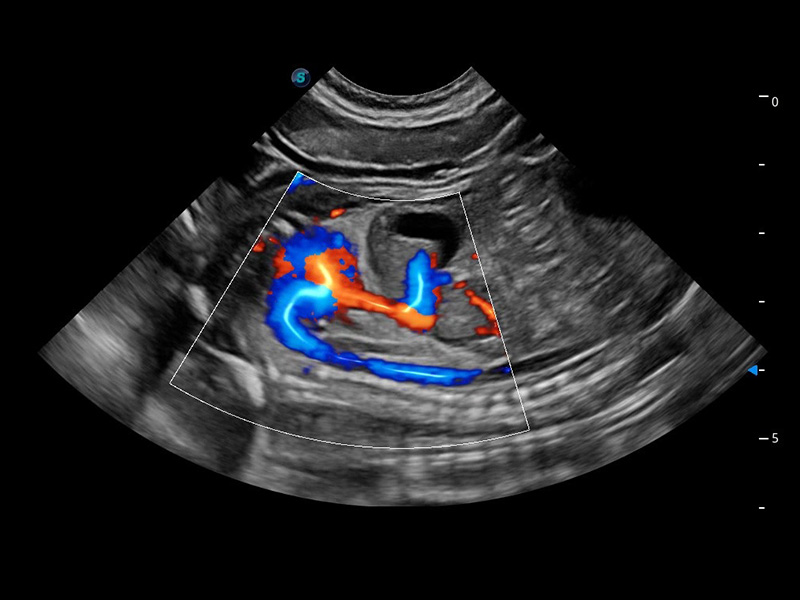

Bright Flow 立体血流成像

在传统二维血流成像的基础上,呈现血流的立体感,具有动感的生命力之美。精确区分不同血管的空间关系,提高了血流的视觉敏感性。

优异的基础图像

(犬)四腔心血流